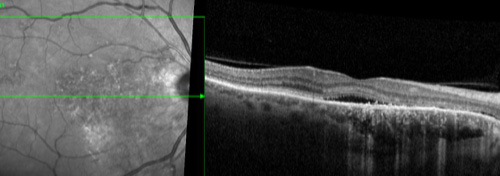

Central serous chorioretinopathy (CSCR) is a condition in which fluid accumulates under the retina and might cause vision loss. This occurs most commonly in young and middle-aged adults. Men usually develop this condition more commonly than women. Vision loss is usually temporary but sometimes can become chronic or recur.